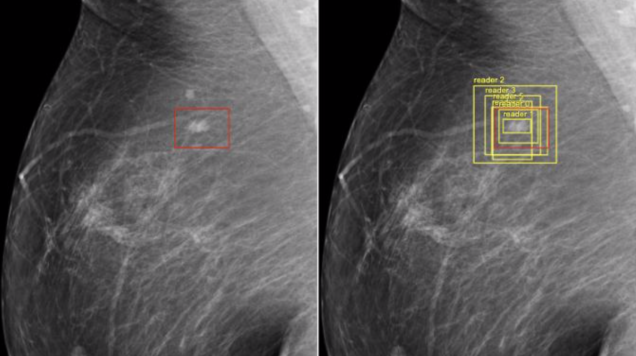

Google, in its bid to move into healthcare, reports that researchers have successfully trained AI to detect breast cancer with greater accuracy than doctors. In a Google-funded study, a team of independent researchers from various hospitals and universities, researchers from Google Health, and engineers from DeepMindā¦

Source: Gizmodo – Google’s AI Proves Better at Detecting Breast Cancer Than Doctors